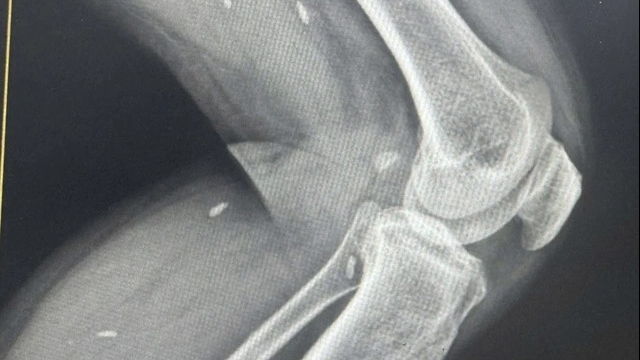

Khi vào Khoa Cấp cứu, Bệnh viện 19 - 8 (Bộ Công an), bệnh nhân tỉnh, tiếp xúc tốt, có xây xát vùng gò má và hai bàn tay, đau ngực trái, mạch và huyết áp ổn định. Khám cận lâm sàng ghi nhận gãy xương sườn 4, 5, 7 bên trái’ gãy rạn cung tiếp gò má trái và gãy thành trước xoang hàm trái. Siêu âm bụng chưa phát hiện tổn thương.